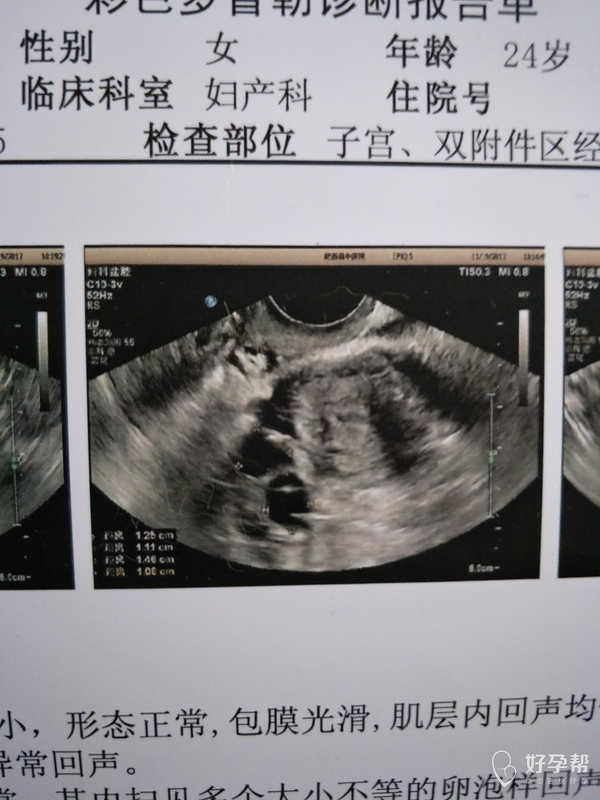

19号在中医院做的就是图片上面的有两个优势

内膜6

11+15

11+13